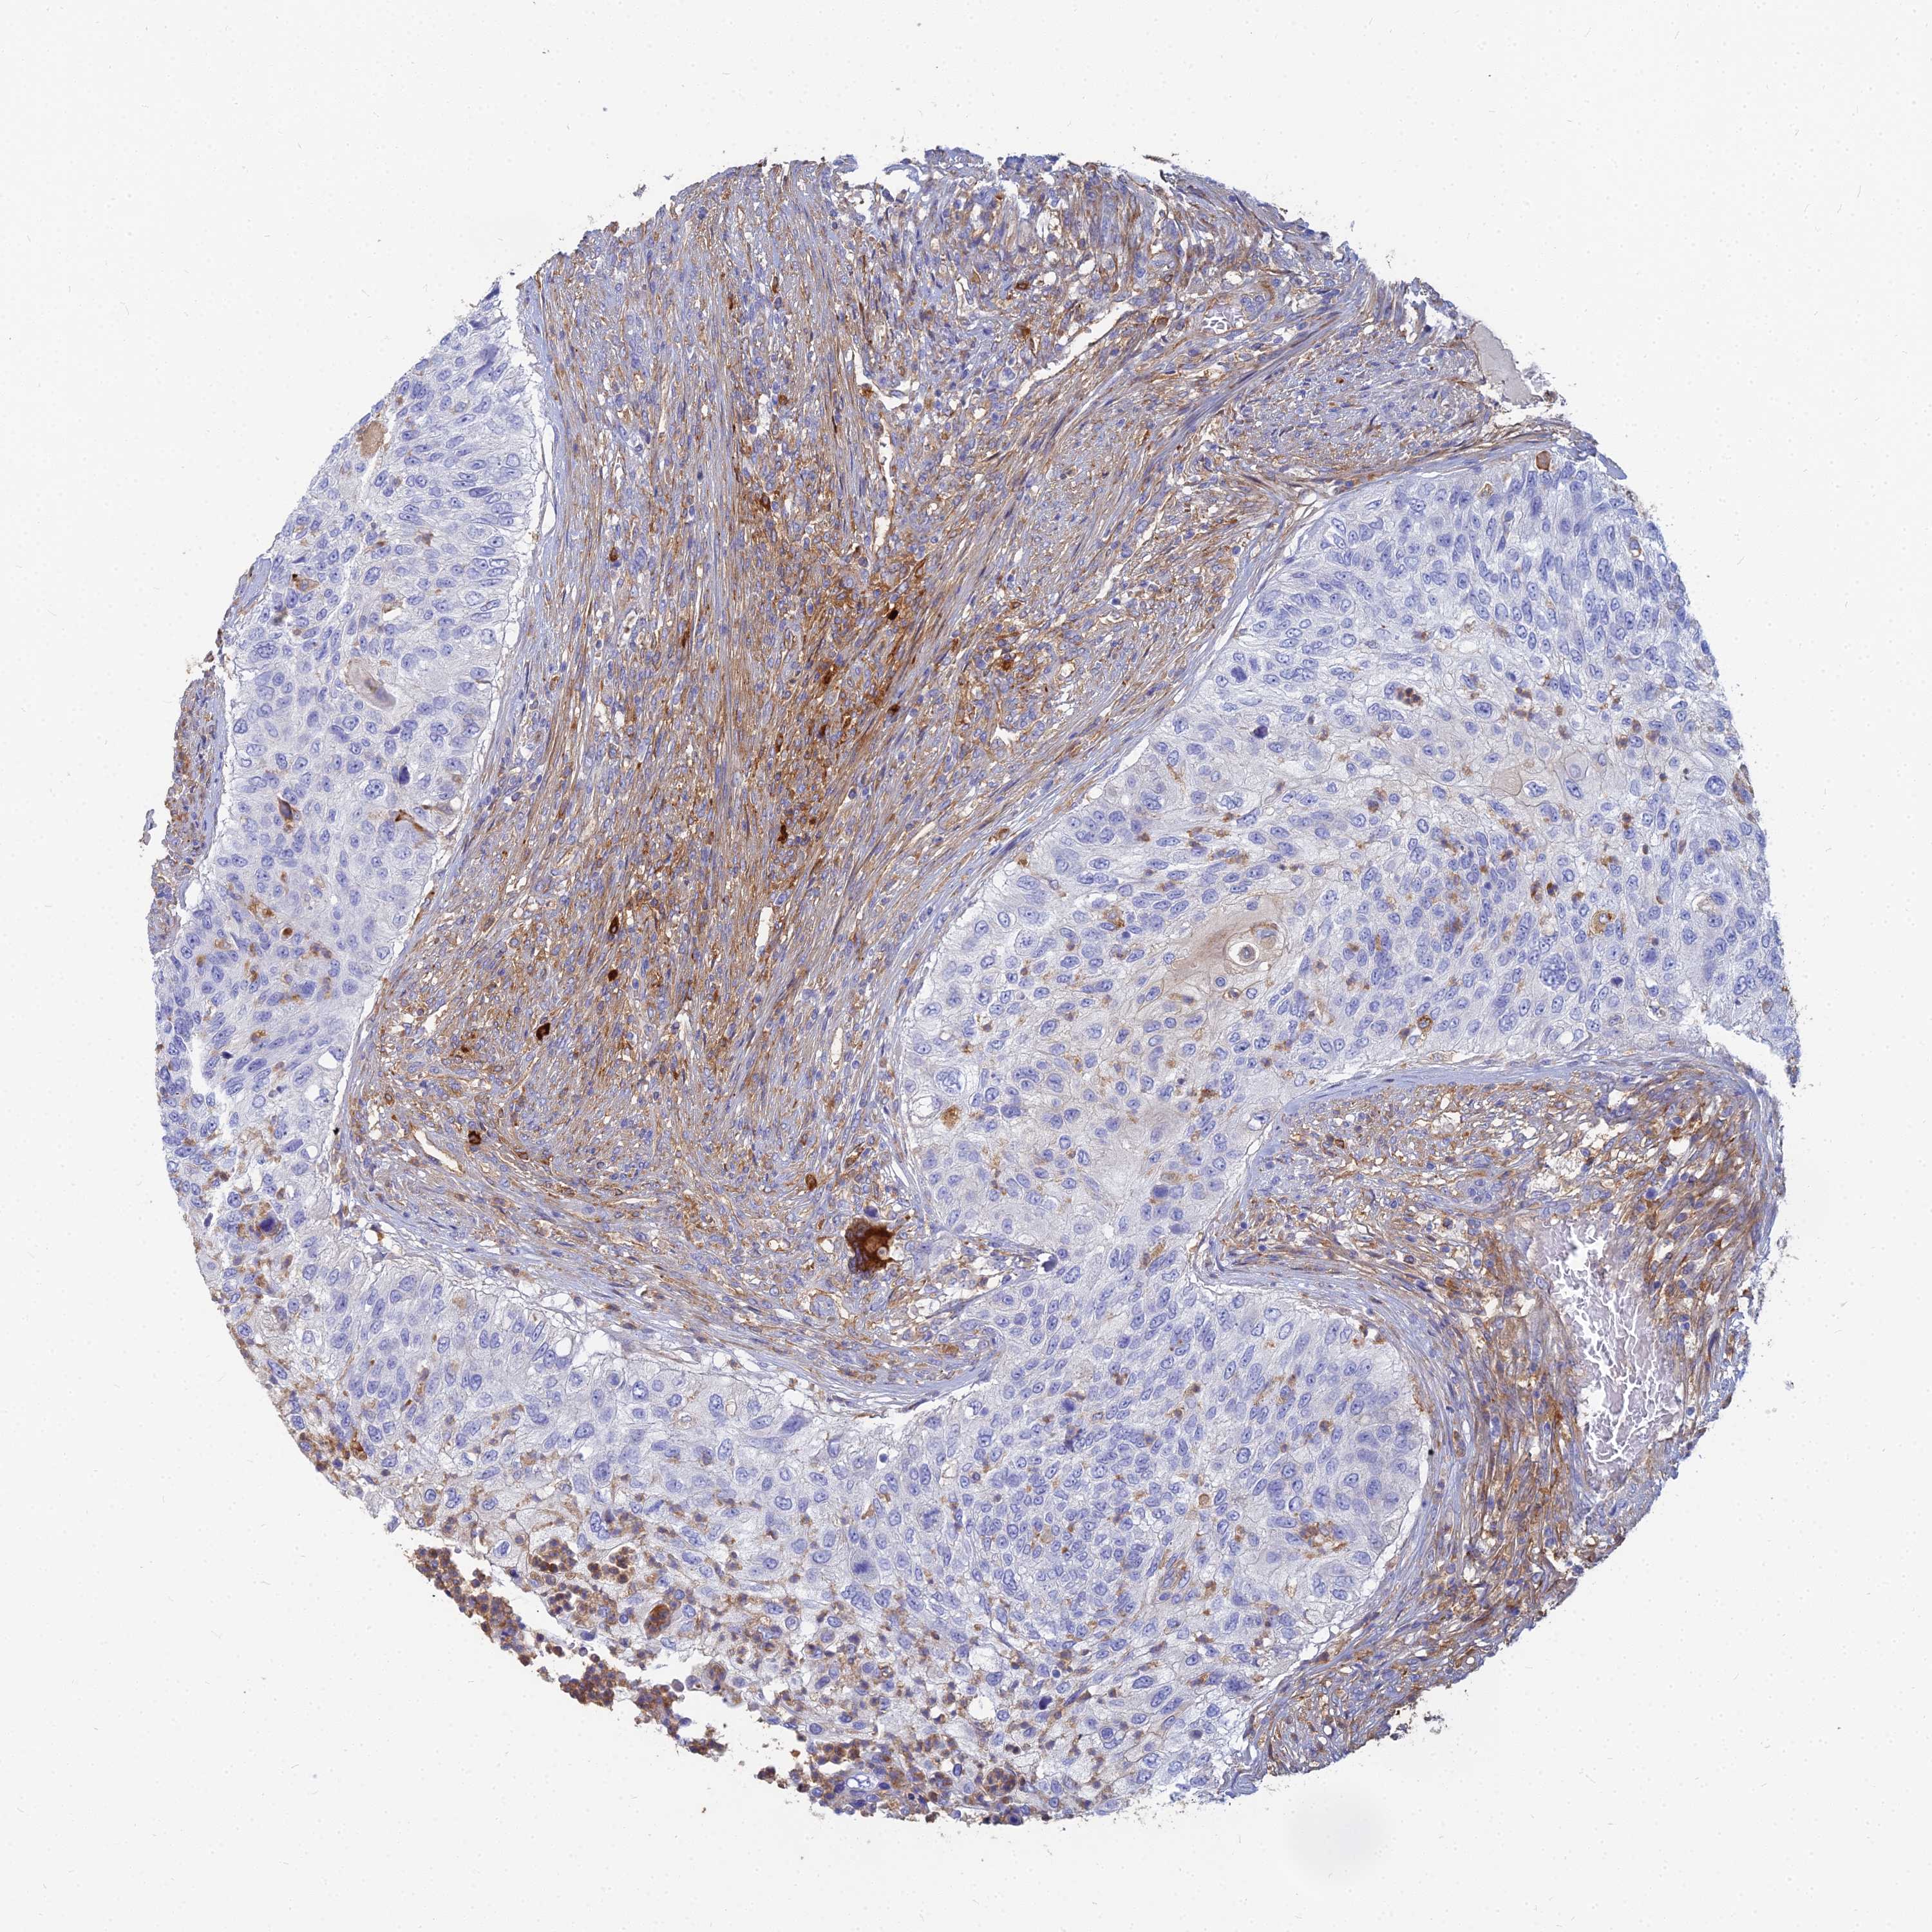

UROTHELIAL CANCER - Protein expressioni

A mouse-over function shows sample information and annotation data. Click on an image to view it in a full screen mode. Samples can be filtered based on level of antibody staining by selecting one or several of the following categories: high, medium, low and not detected. The assay and annotation is described here.

Note that samples used for immunohistochemistry by the Human Protein Atlas do not correspond to samples in the TCGA dataset.

Antibody stainingi

Antibody staining in the annotated cell types in the current human tissue is reported as not detected, low, medium, or high, based on conventional immunohistochemistry profiling in selected tissues. This score is based on the combination of the staining intensity and fraction of stained cells.

Each image is clickable and will lead to virtual microscopy that enables deeper exploration of all samples and also displays staining intensity scores, fraction scores and subcellular localization as well as patient and tissue information for each sample.

Antibody HPA045170

Staining

High

Medium

Low

Not detected

Intensity

Strong

Moderate

Weak

Negative

Quantity

>75%

75%-25%

<25%

None

Location

Nuclear

Cytoplasmic/membranous

Cytoplasmic/membranous,nuclear

Urothelial carcinoma, High grade

Urothelial carcinoma, Low grade